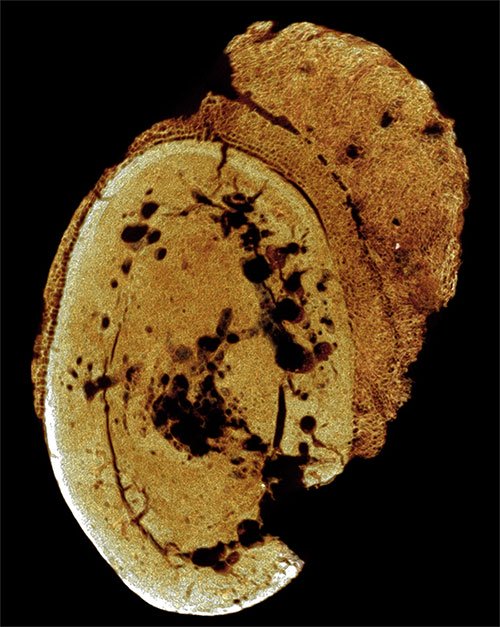

Theo tài liệu của Hiệp hội Ung thư Mỹ, con người và động vật đã bị ung thư rất lâu trong quá khứ. Bằng chứng sớm nhất về ung thư được tìm thấy trong khối u xương hóa thạch của một xác ướp 1,6-1,8 triệu năm trước, tại một hang động ở Nam Phi.

Tế bào ung thư trong hóa thạch xương ngón chân trái 1,6 - 1,8 triệu năm tuổi. (Ảnh: Patrick Randolph-Quinney, UCLAN).

Tuy nhiên, số lượng những tế bào ung thư cổ xưa như vậy được tìm thấy cũng rất hiếm. Năm 2016, nhóm nghiên cứu của giáo sư Michael Zimmerman (Đại học Villanova ở Pennsylvania, Mỹ) đã thực hiện phân tích hàng trăm xác ướp ở Ai Cập.

Trong số đó, chỉ có một trường hợp ung thư được xác nhận. Đó là tế bào ung thư đại trực tràng. Các thí nghiệm này cho thấy việc ướp xác không phá hủy bằng chứng về khối u ác tính. Do đó, tỷ lệ người cổ xưa mắc ung thư rất ít.